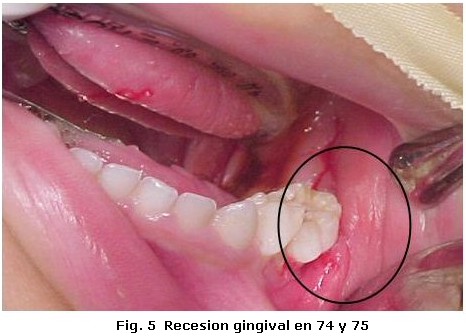

Un varón de tres años de edad con diagnostico de Histiocitosis de Células de Langerhans con afección ósea multifocal y otros sitios especiales fue referido al Servicio de Odontopediatría del Hospital Universitario de Maracaibo por el Servicio de Oncología Pediátrica del mismo Hospital, para valoración. El examen médico reveló, exoftalmos, palidez mucocutánea con pápulas eritematosas, lesiones hipercrómicas en miembros inferiores, dermatitis seborreica en cuero cabelludo, múltiples adenopatías cervicales y otitis supurativa recurrente. El informe de las pruebas de laboratorio indicó anemia y diabetes insípida. La biopsia de cuero cabelludo y el estudio inmunohistoquímico de la muestra tomada (Figura 1, 2 y 3) confirmaron el diagnóstico clínico, mientras que el examen de líquido cefalorraquídeo y médula ósea reportaron ausencia de infiltración. En las imágenes de resonancia magnética cráneo-facial, se evidenció realce anormal sugestivo de infiltración de huesos de base craneana y fosa anterior y media, mientras que la tomografía axial computarizada, reportó ausencia parcial de arco cigomático del lado derecho e imágenes osteolíticas en hueso temporal y pared orbitaria externa del mismo lado, acompañadas de lesiones similares en techo de orbita del lado izquierdo (Figura 4). Otros estudios, como tomografía de abdomen, pelvis y tórax, electroencefalograma, Rx de huesos largos, tórax óseo y columna, no revelaron hallazgos de interés. Durante la evaluación odontológica, la exploración extraoral evidenció exoftalmos y las lesiones de piel antes descritas; intraoralmente se registró la presencia de placa dental, gingivitis y hemorragia (Tabla 1), acompañada de movilidad dental, bolsas periodontales y recesión gingival (Figura 5) en la zona posterior izquierda de ambos maxilares (Tabla 2), además de caries dental y erupción prematura del 26. Radiograficamente se observaron lesiones osteolíticas, de bordes mal definidos, que medían aproximadamente entre 0,5 y 1,5 cm. de diámetro, localizadas en relación al 64, 65, 26, 74, 75, 85, también se observó agenesia de los gérmenes del 35 y 45 (Figura 6). Para el momento de la evaluación odontológica el paciente estaba recibiendo tratamiento con vasopresina y quimioterapia con vinblastina y prednisona. El manejo odontológico incluyo una fase inicial preventiva en la cual se instruyo a los representantes y al niño sobre hábitos de alimentación, higiene bucal y técnicas de cepillado y una fase quirúrgica llevada a cabo bajo anestesia general. Previa valoración sistémica y premedicación con antibioticoterapia se realizaron exodoncias del 65, 26, 74, 75 y curetaje de las lesiones. El resultado de la biopsia del tejido encontrado en los maxilares reportó un infiltrado inflamatorio severo, constituido por acumulo de linfocitos, histiocitos espumosos y células plasmáticas, mientras que el estudio inmunohistoquímico realizado con proteína S-100 y CD1a resultó negativo. Después de dos meses de seguimiento, el paciente cicatrizó favorablemente con persistencia en el 64 de recesión gingival, exposición de dos tercios de la raíz distal y movilidad leve. Radiograficamente se observan signos de osificación en las zonas intervenidas, sin embargo, es necesario seguir monitoreando al paciente para descartar la aparición de nuevas lesiones (Figura 7).

La Histiocitosis es una rara enfermedad cuyas manifestaciones clínicas son muy variadas; en el caso reportado, las características clínicas coinciden con algunas típicamente descritas en la literatura en relación a la edad, dermatitis seborreica, diabetes insípida, exoftalmos y lesiones óseas multifocales1-4. Este último tejido es uno de los más afectados1, nuestro paciente presentó lesiones en ambos maxilares y de forma bilateral en mandíbula, aunque en mayor grado del lado izquierdo. Desde el punto de vista clínico estas lesiones pueden semejar enfermedad periodontal y provocar movilidad dental2, la afectación ósea en nuestro paciente provocó erupción prematura del 26, recesión gingival y grado severo de movilidad dental; situación agravada por la presencia de irritantes locales. Un hallazgo que no hemos podido constatar con la literatura revisada, es la ausencia de los gérmenes del 35 y 45 sin relación con historia familiar, la cual podría catalogarse como agenesia, ya que de acuerdo a la secuencia y cronología dental, a los tres años edad deberían observarse signos de su formación7. Por otra parte, la ausencia bilateral de los gérmenes y la presencia de importantes lesiones osteolíticas solo en relación al 35, descarta la posibilidad de que las células infiltrantes hayan sido responsables de hallazgos similares en el lado contralateral donde la lesión era inferior a 0,5 cm. Sin embargo, es necesario descartar otros factores responsables de la agenesia dental antes de definir su etiología. El estudio inmunohistoquímico realizado a la lesiones intraorales no reveló positividad para S-100 y CD1a, a pesar de haberse encontrado positivos en la biopsia a inicial de cuero cabelludo. Estos marcadores además del CD207 han sido catalogados como específicos para la determinación de células de Langerhans; sin embargo se ha reportado hasta un 13% de resultados negativos para CD1a y un 7% para el CD2078. Los resultados obtenidos en la inmunohistoquímica de las lesiones maxilares, también podrían estar relacionados con los efectos producidos por la quimioterapia sobre las células infiltrantes. No obstante otros factores relacionados con la toma de la muestra no pueden descartarse como responsables de estos hallazgos. La decisión de seleccionar la cirugía, quimioterapia y/o radiación como tratamiento en la histiocitosis, dependen de la extensión de las lesiones, el grado de tejido involucrado y de la presentación unifocal o multifocal1,3. En este caso se decidió realizar exodoncias de los dientes con grado de movilidad severa y curetaje, con el fin no solo de tratar las lesiones maxilares sino de controlar el riesgo de infección. Se concluye que los maxilares al igual que los huesos del cráneo deben ser evaluados en pacientes con diagnóstico de Histiocitocis de Células de Langerhans, ya que estos pueden ser los únicos huesos afectados como sucedió en el caso estudiado. Por otra parte es importante resaltar que a pesar de la importancia de las pruebas inmunohistoquimicas en el diagnostico de esta enfermedad, su resultado siempre debe ser correlacionado con los hallazgos clínicos, radiográficos e histológicos encontrados en cada caso en particular.